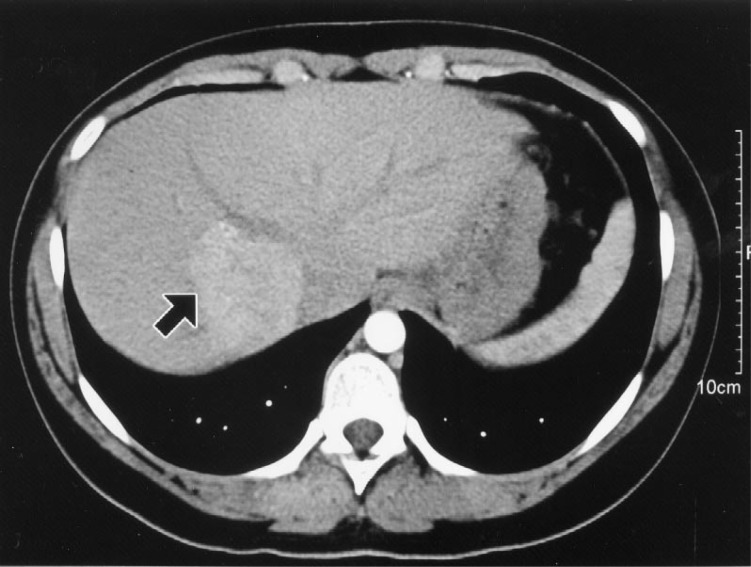

CT scan has a reduced detection rate of hepatocellular carcinomas in patients with . . .

. . . cirrhotic livers

Cirrhosis makes it difficult to visualize the interior of the liver as well as you would otherwise

Triple phase CT scan

CT scan with IV contrast that acquires images at 30 seconds (arterial), 60 seconds (portal-venous), and 90 seconds (equilibrium)

Alows for better characterization of liver lesions